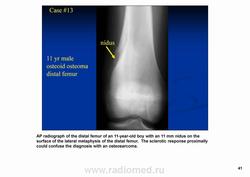

Остеоидная остема.

Диагностика и дифференциальная диагностика.